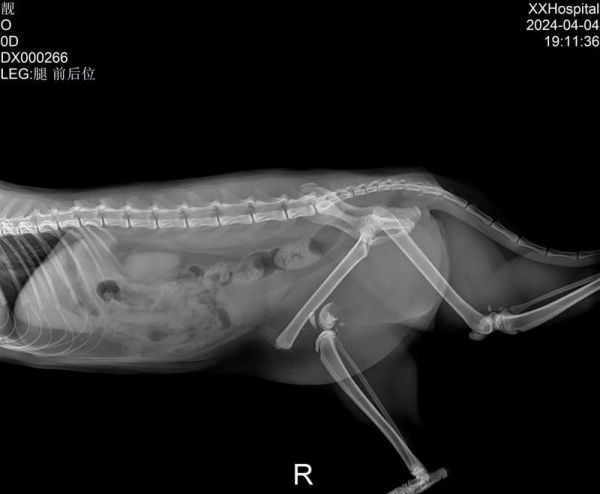

猫在日常生活中不可避免地会遇到一些意外情况导致骨折的情况,而内固定手术是治疗猫骨折的常见方法之一。然而,很多猫主人对于猫骨折内固定术后的康复时间缺乏清晰的了解。本文将深入探讨猫骨折内固定术后康复的时间长度及相关注意事项。